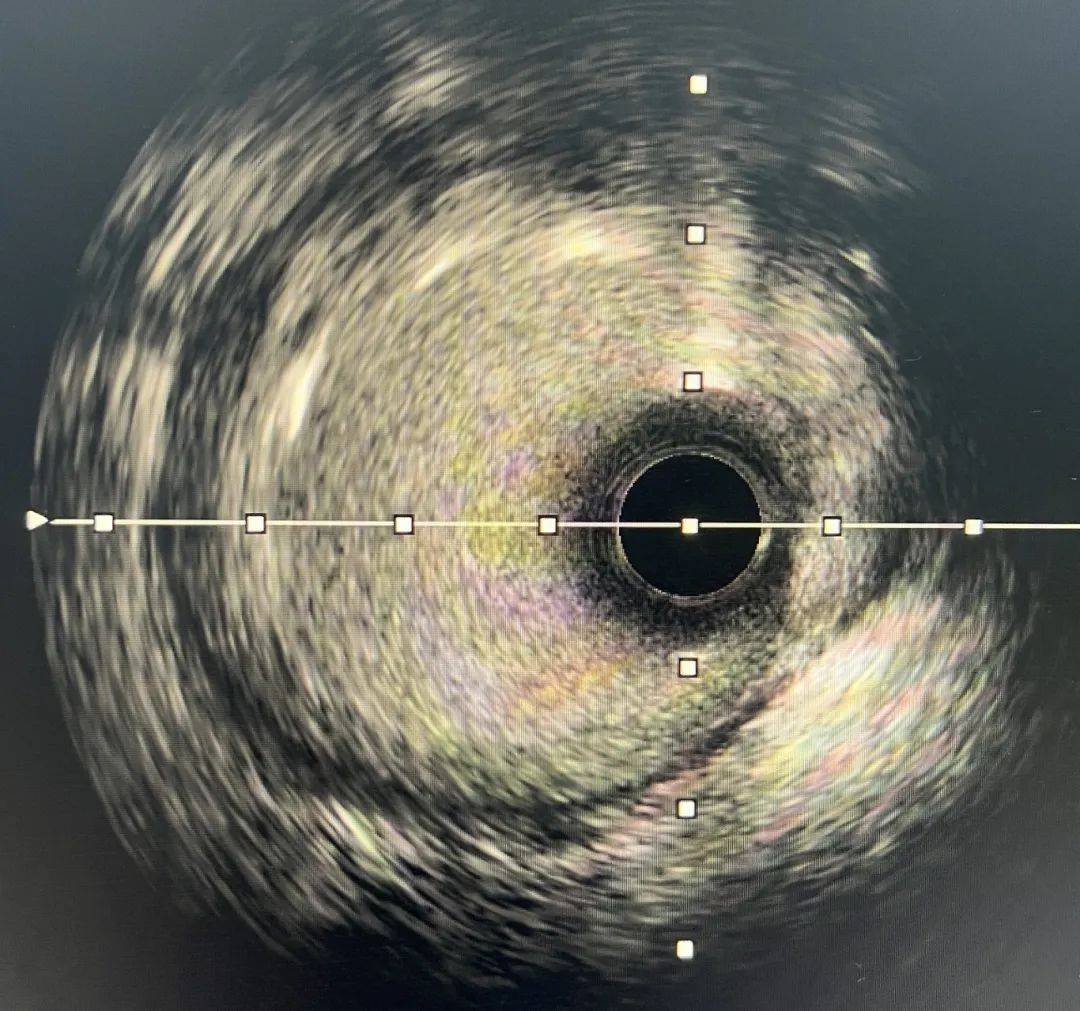

高效「心」技術——「無煙PCI」

無煙PCI就是不使用造影劑的介入技術,醫生應用IVUS(血管內超聲),充當「眼睛」指導手術,這對手術團隊是一項挑戰。造影劑在冠脈介入手術過程中就是醫生的透視眼,採用「無煙技術」對血管、導絲、球囊、支架的定位要求極高,術者必須有對冠脈疾病的理解及冠脈腔內影像學過硬的技術,才可以成功完成手術。

術中,介入團隊在院長林海龍的指導下,對王大爺實施IVUS檢查,發現右冠脈中段嚴重狹窄,斑塊負荷86%,應用多導絲定位及解剖定位方式,精準測量,在未使用1滴造影劑的情況下,僅用時40分鐘成功為患者植入2枚支架,複查IVUS提示狹窄解除,支架貼壁良好。術後患者胸痛症狀緩解,順利出院。